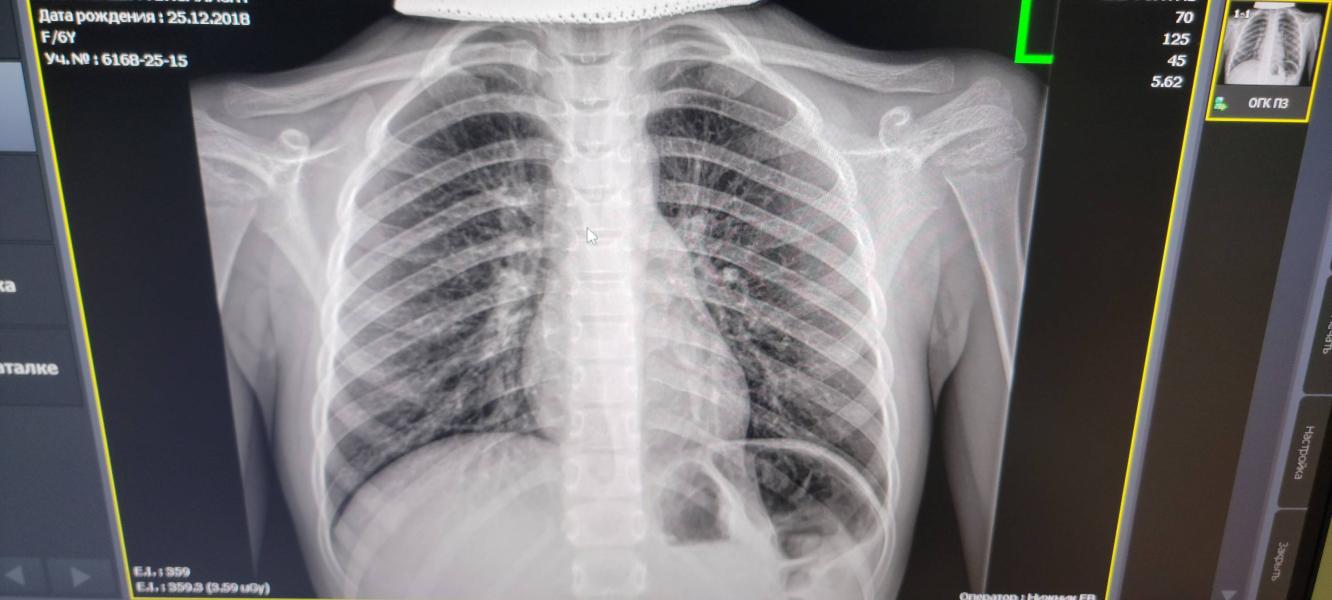

Я бы сказала что очень похоже на вирусную пневмонию , не бактериальную . Очень четко выражен легочный рисунок . Но я не врач , но снимки , кт и МРТ почитать люблю

Температура не высокая три дня ,кашель мокрый ,особенно ночью прям до рвотного рефлекса сейчас

Пневмонию на снимке видела 2 раза у обоих своих детей, и мне на вашем снимке похоже, что она((( только не расстраивайтесь раньше времени, мы тут не врачи